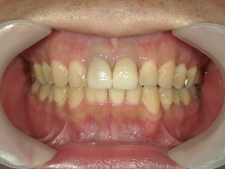

矯正歯科 治療後矯正歯科 全顎ワイヤー矯正 治療後矯正歯科(全顎ワイヤー矯正)治療後

矯正歯科 治療後 E-AMXというセラミックにて左右上1番を被せ直しました。